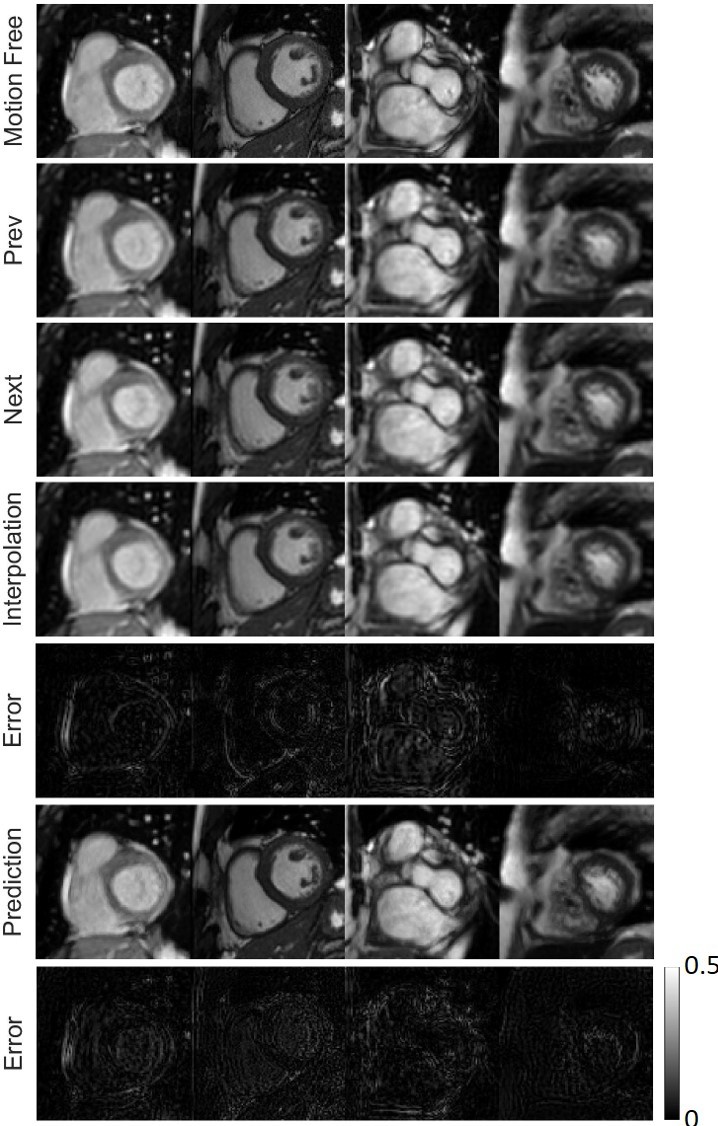

Refer to caption

Figure 8: Frame prediction results on the ACDC dataset. First row: motion-free ground truth images. Second row: previous motion-blurred frames. Third row: next motion-blurred frames. Fourth row: simple average interpolation frames. Fifth row: error maps between simple average interpolation frames and motion-free frames. Six row: our network-predicted frames. Seventh row: error maps between our predicted frames and motion-free frames. All the error maps are shown on the same grey scale bar.

Fig. 8 presents the frame interpolation results. Given an incomplete motion-blurred cine cardiac MRI sequence, our network can predict missing frames, clearly outperforming the linear interpolation of the previous and next frames. It can be seen that the position and shape of the ventricle structures in our predicted missing frames are quite close to the target ground truth frame. In addition, compared to the previous and next frames, the image quality of the prediction is greatly improved.